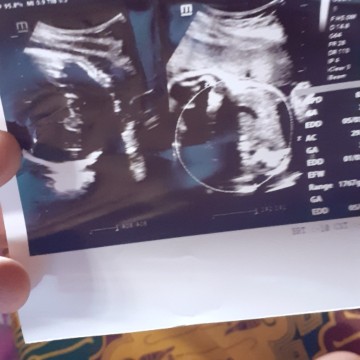

ap pnjelasan usg ni bunda aku gak gerti

usg ni apa pnjlasan ya bunda